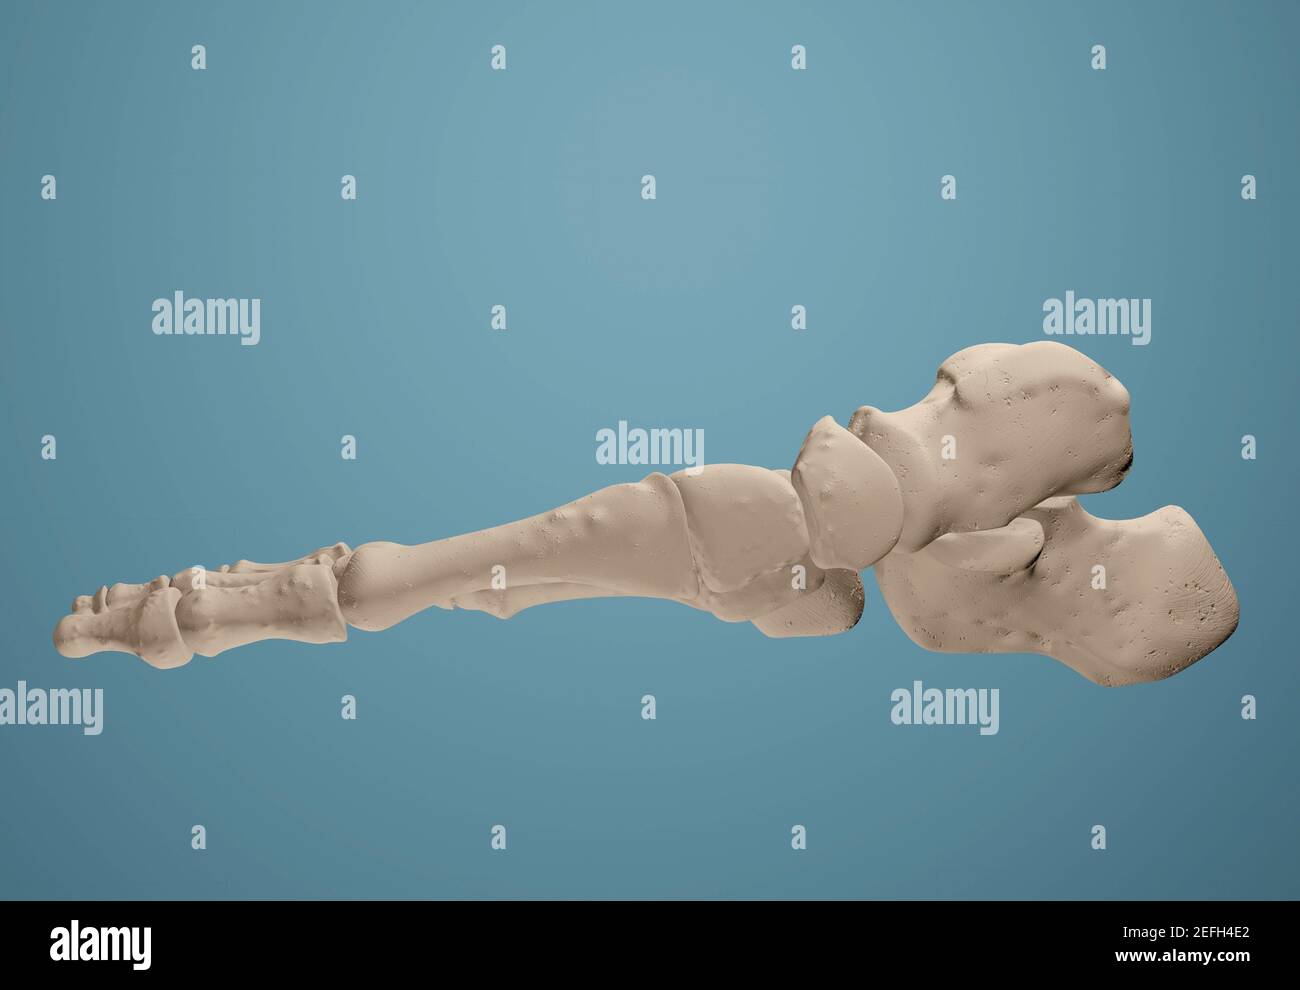

RF2GMNAX6–Vue latérale externe du squelette d'un pied humain articulé, avec la partie distale du tibia et du péroné montés sur un fil. Concept anatomique